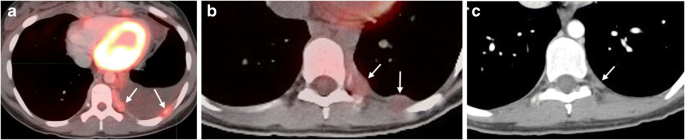

Fig. 5

figure 5

Example of complex effusion. a Pre-study PET/CT exam in a 14-year-old girl demonstrates FDG PET avidity in pleural nodules with associated moderate effusion. b, c Imaging in a 16-year-old girl with two nodules seen initially on an axial PET/CT image (b), with one small residual post-therapy nodule as seen on an axial CT image (c). FDG [F-18]2-fluoro-2-deoxyglucose, PET/CT positron emission tomography/computed tomography

Ten of the 13 patients with associated solid components were evaluated by FDG PET and three were evaluated by gallium. Of the 10 who were evaluated by FDG PET, all nodules and adjacent involved lung or bone were PET-avid. Those who had gallium scans showed no gallium positivity in any lesion.